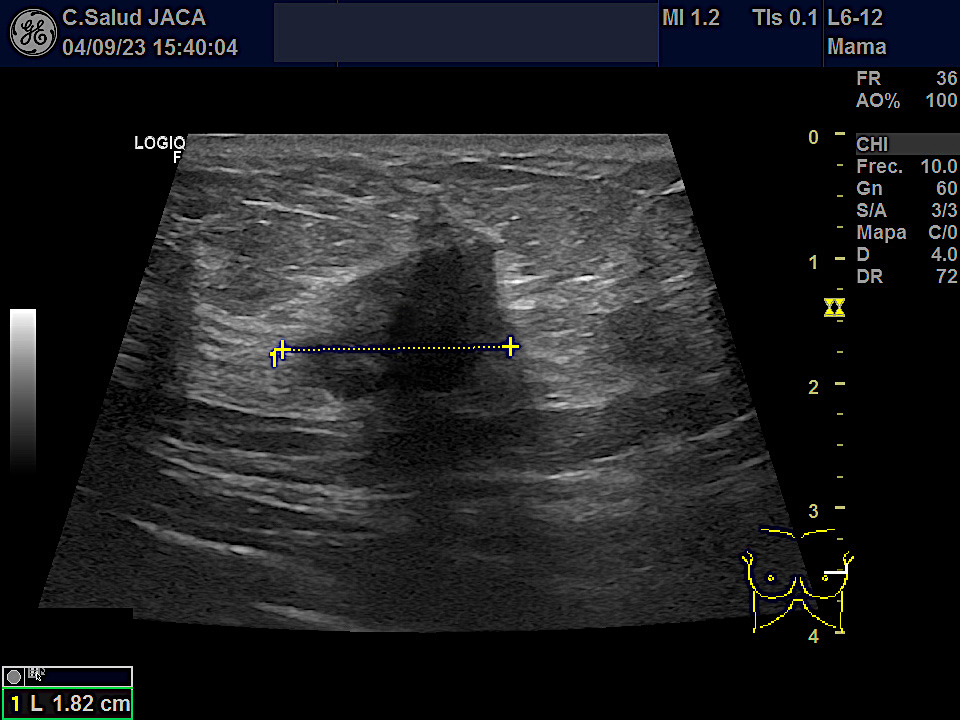

Mostramos las imágenes ecográficas de cada una de esas 5 neoplasias obtenidas desde la Atención Primaria, en modo 2D y tras estudio Doppler. Los tumores variaban de 8 a 30 mm en su eje mas largo. Salvo uno, el resto mostraba características típicas: bordes irregulares, espiculados, estructura hipoecogénica, actividad Doppler interna y ausencia de refuerzo posterior.